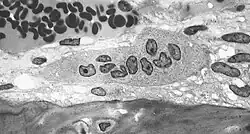

Osteoklast je velká rozvětvená kostní buňka schopná pohybu. Bývá mnohojaderná, obsahuje až 50 jader. Není jasné, jakým způsobem vzniká, dříve se soudilo, že má stejný původ jako ostatní kostní buňky, ale výzkumy ukazují, že se vyvíjí z monocytů, konkrétně zřejmě fúzí několika těchto buněk. Mívají rozvětvený povrch a množství buněčných organel, jako je rozvinuté drsné ER, Golgiho aparát a lysozomy.